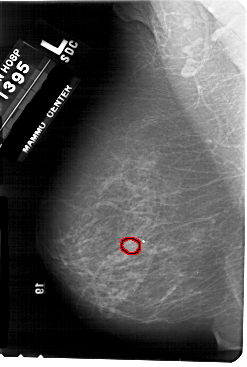

A_1676_1.LEFT_MLO

LEFT_MLO LINES 5491 PIXELS_PER_LINE 3691 BITS_PER_PIXEL 12 RESOLUTION 43.5 OVERLAY

FILE: A_1676_1.LEFT_MLO.OVERLAY

TOTAL_ABNORMALITIES 1

ABNORMALITY 1

LESION_TYPE MASS SHAPE OVAL MARGINS OBSCURED

ASSESSMENT 4

SUBTLETY 3

PATHOLOGY MALIGNANT

TOTAL_OUTLINES 1

BOUNDARY